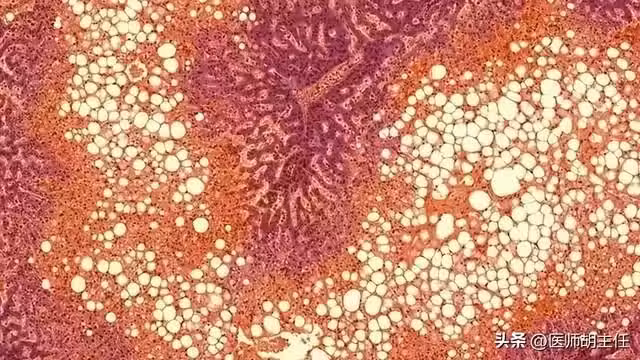

長期由於肝內的脂肪積累過多會引起肝細胞的病理改變,在鏡下顯示為肝細胞內充滿了大的脂肪滴,大體觀上肝臟表面油膩,切緣變鈍,脂肪變性隨著病程進展會影響肝臟的正常代謝。

如果不進行積極的干預,脂肪肝加重可以導致肝纖維化,纖維相較於正常組織更為堅硬,這就是肝硬化。

肝硬化不僅影響正常代謝,癌變機率也大大提高。 肝臟由各種原因導致脂肪變性總稱為脂肪肝,脂肪肝最常見的為酒精性脂肪肝。